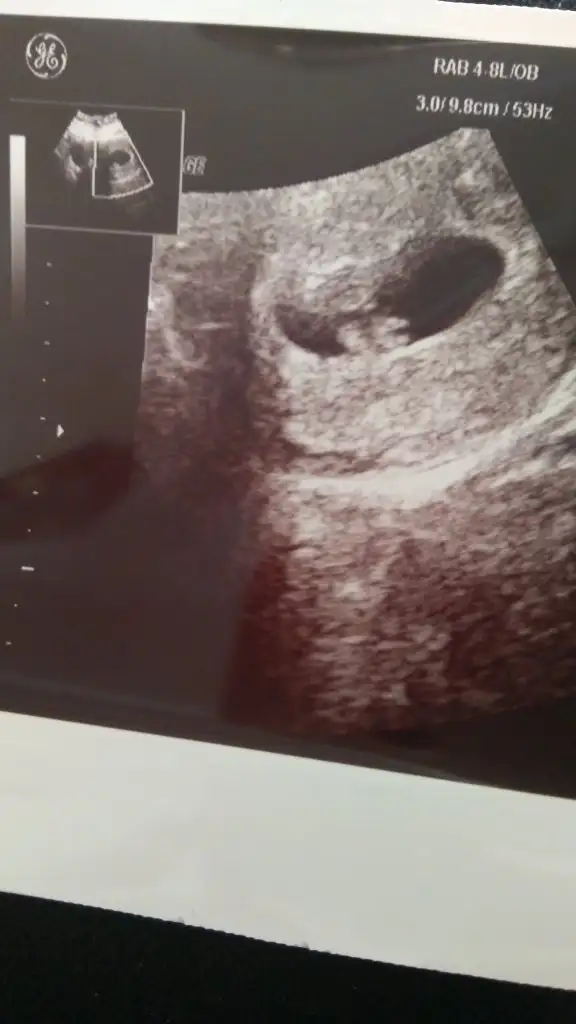

Benim batı 2 gün geçtiğinde 24 tü, sonra arttı düzenli. takip ettiğim kadarıyla ilk defa geç yumurtladım ve onda da hamile kaldım. sonra düzenli arttı ve keseyi gördük. yarın da kalp atışı için gidicez. takip edersiniz, inşallah güzel güzel artar değeriniz